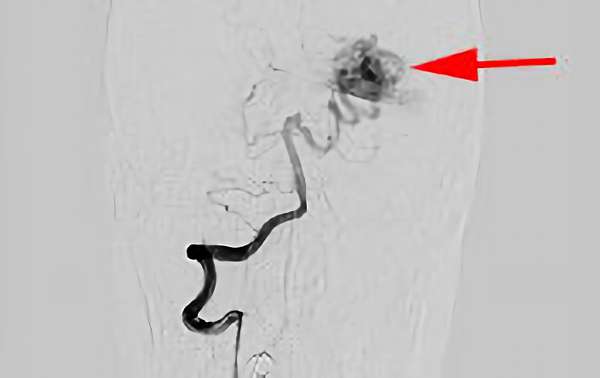

'25年9月

脳動静脈奇形

20代

愛知県の病院

No.1576 手術前

No.1576 手術中

No.1576 手術後